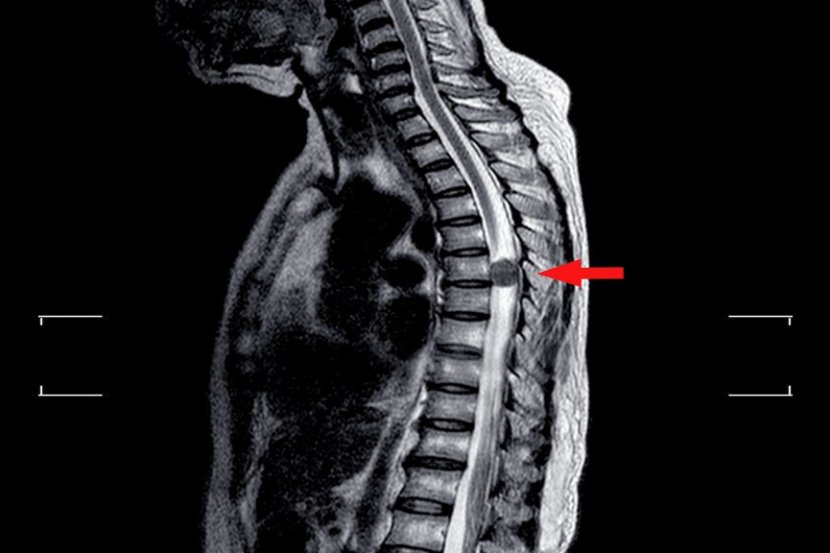

Sinovijalna cista kičme je vrećica ispunjena tečnošću, koja se se razvija duž kičmenog stuba. Rezultat je benigne degeneracije međupršljenskih zglobova (fasete) kičme. Sinovijalna cista na kičmi se zapaža najčešće u donjem delu leđa. Ove ciste u kičmenom stubu uglavnom nisu praćene simptomima, ali nekada mogu uzrokovati probleme, kao što je spinalna stenoza.

Ukoliko se pacijent požali na bolove u leđima lekar može savetovati rendgenski snimak kako bi se isključila mogućnost drugih problema. Cista se lako prepoznaje na magnetnoj rezonanci, izgleda kao mehur u blizini fasetnog zgloba. Kada lekar utvrdi položaj i veličinu ciste napraviće plan lečenja.